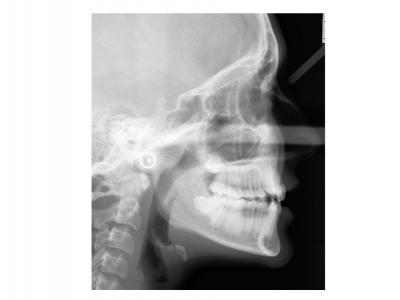

Voici les deux patientes traitées

Ici, dans les deux cas, les deuxièmes prémolaires ont été extraites et les traitements ont duré 18 mois.

Dans le premier cas, la béance s'est fermée spontanément (pas prévu au départ) sans rééducation, sans appareil de contrainte linguale, ni élastique. Il semblerait que le gain de place a permis aux incisives de se redresser spontanément et donc de fermer la béance. La fermeture de la béance, la normalisation de l'environnement anatomique a permis à la langue de se mettre à travailler correctement. Pour le sens transversal, la correction a été aussi spontanée. Juste une minivis dans le secteur 1 a été placée pour recentrer mon milieu (ancrage maximal recherché au départ). Les finitions auraient pu être meilleures. Elle finit avec une légère classe II (on va dire qu’elle est surcorrigée :)). Le traitement a terminé plus tôt que prévu (24 mois annoncé), car problèmes de santé.